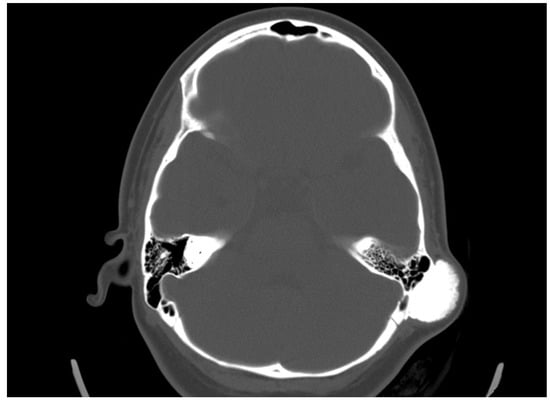

The diagnosis is made by performing a computed tomography scan, with a clear presentation of the size, density, and boundaries of spread (Figure 1). In the presented clinical case, we establish a mastoid process osteoma with slow progression for a period of 6 years, creating only a cosmetic defect in the retroauricular area.

The clinical course of osteomas is often asymptomatic, and they are usually diagnosed incidentally. Depending on the localization, they may present with facial deformities, ocular manifestations (exophthalmos), and headaches [7]. The diagnosis of osteomas can be made by skull radiography/skull X-rays (occipitomental projection, also known as Water’s view) or computed tomography without contrast enhancement, which has many more advantages. Computed tomography with 3D reconstructions allows for the detailed visualization of osteomas and their specific localization in relation to other vital structures (the orbit, anterior, medial, and lateral skull base, facial nerve and intracranial structures). It can also determine the attachment of the osteoma to the cortex in the case of mastoid processes—pedunculated or sessile [8]. The study is also useful in the differential diagnosis of osteoma and other mastoid bone tumors, especially osteosarcoma, bone metastases, multiple myeloma, giant cell tumor, Paget’s disease-associated lesions, or fibrous dysplasia [1,6,7,9]. Signs suggesting a malignant lesion are rapid growth, local pain, and a poorly differentiated, heterogeneous, osteolytic appearance on CT [9]. Mastoid osteomas are slow-growing and can seldom be indicated for surgical treatment in the early stages. The cosmetic defect that they would create is the most common reason for surgical removal. Osteoma removal is performed through a retroauricular incision exposing the tumor and its radical removal using a curette or burr. The presentation of intact mastoid cells is normal and does not pose a risk. Sometimes, a slightly prominent sinkhole can possibly occur postoperatively in this area. Histological examination is important to confirm the diagnosis and specify the histological type—compact, spongy, or mixed. Compact or combined is most often found, and spongy is much less common [10].

Figure 1. Radiological examination in front and side view, with the detection of a slight deformation along with bone growth in the cortical area of the mastoid process, pointed with orange arrow.